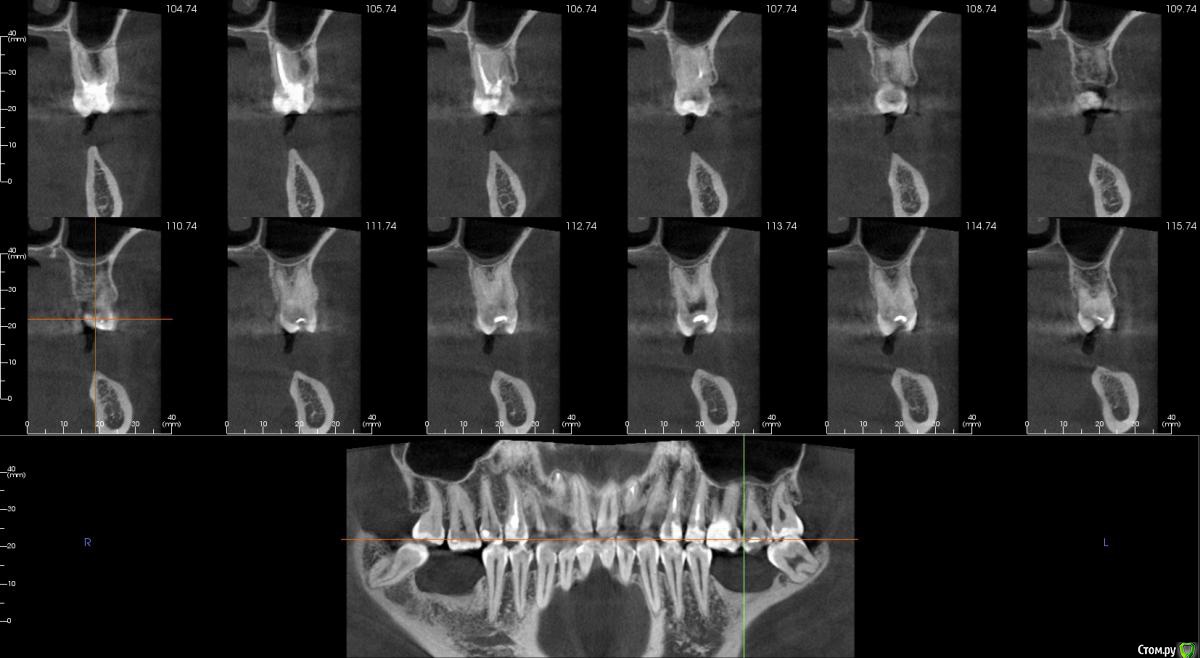

Господа как лучше тут поступить? поменьше бы рисков)

" всеводинэтап"крыша гаража" и латерализация отменяются)))

вижу вариант только с сеткой.

Из того что разобрал по срезам мне кажется можно медиально расщепить и притопить, дистально 4х6 поставить (астра, штрауманн...). Посмотрите, помещаются ли такие импланты. Травма меньше, быстрее и меньше рисков.